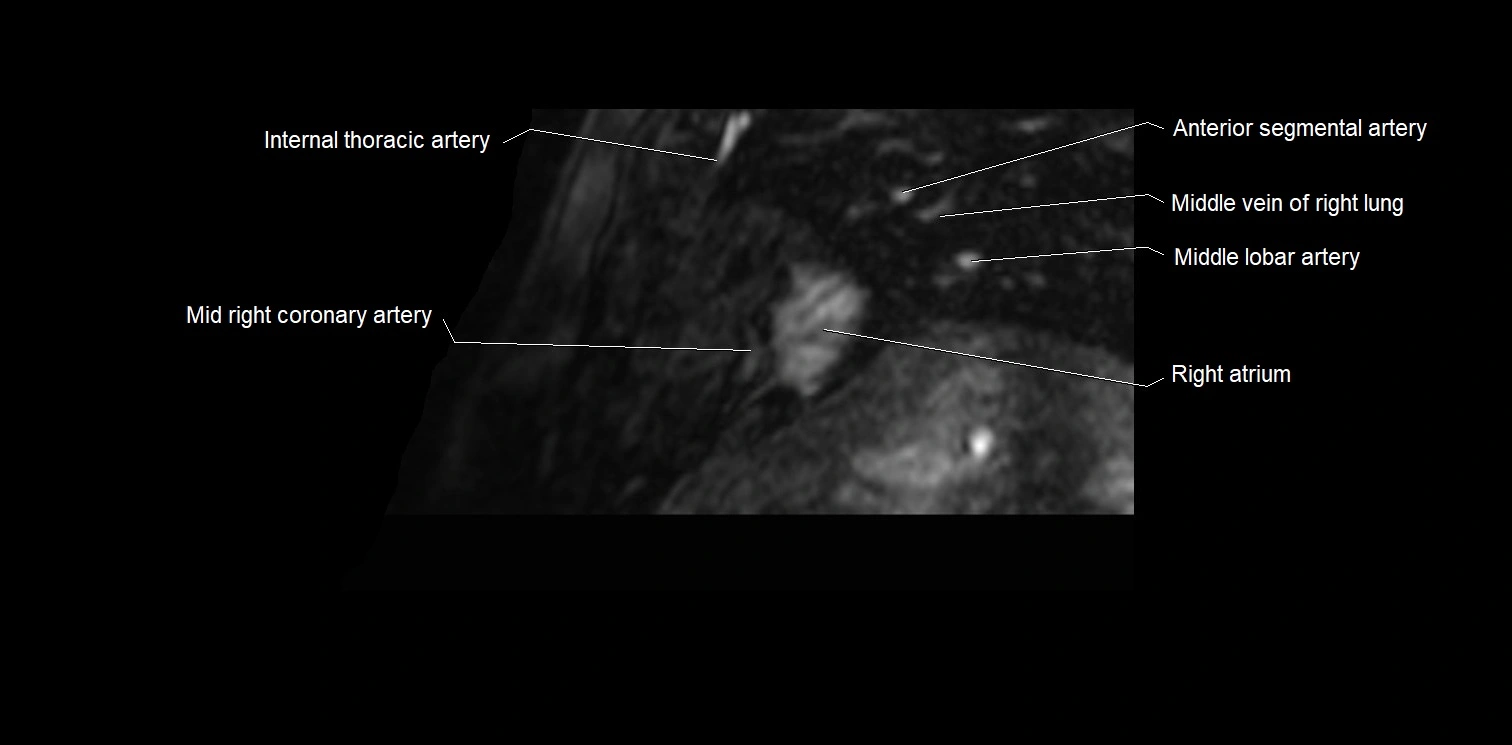

MRI image